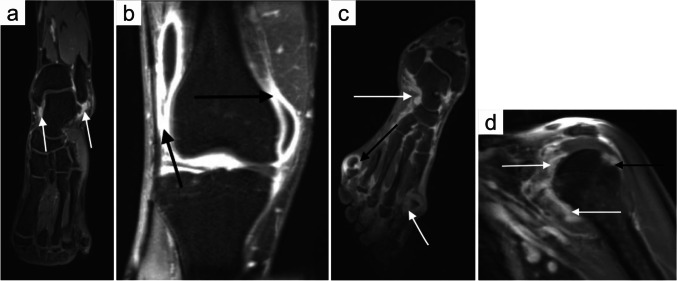

全身MRI (wbMRI)是一种先进的扫描方式,可提供全身的高对比度分辨率图像,用于筛查、诊断、分期和监测目的。由于最近的技术进步,wbMRI作为一种诊断和监测全身性关节炎的有价值的工具,由于其广泛的覆盖范围而受到越来越多的关注。这项技术特别适用于炎性疾病,如类风湿关节炎、血清阴性脊椎病、青少年特发性关节炎和慢性无菌性骨炎,这些疾病的特点是骨骼和骨骼外部位多灶受累。与针对症状区域的传统MRI不同,wbMRI能够同时早期发现亚临床疾病病灶,从而更准确地评估总疾病负担。与x线平片、常规超声和靶向MRI相比,wbMRI具有更好的灵敏度和可重复性,特别是在骨内发现和轴向受累方面。此外,通过可定制的扫描方案,wbMRI可以根据特定的临床需求进行定制,并且缺乏电离辐射使其成为监测自身免疫性疾病的理想选择,也适用于敏感人群。虽然wbMRI在提高炎性关节炎的诊断准确性和患者预后方面具有很大的潜力,但需要进一步的研究来验证标准扫描方案,确认其成本效益,并将其纳入常规临床实践。本文旨在概述目前的wbMRI技术,并在炎症性关节炎的背景下讨论它。还提供了非肿瘤学肌肉骨骼应用的一般wbMRI方案。

Whole-body MRI (wbMRI) is an advanced scan modality which provides high-contrast resolution images of the entire body for screening, diagnosis, staging, and surveillance purposes. Thanks to recent technological advancements, wbMRI has gained increasing attention as a valuable tool for diagnosing and monitoring systemic arthritides by virtue of its comprehensive coverage. This technology is particularly beneficial for inflammatory conditions like rheumatoid arthritis, seronegative spondyloarthropathy, juvenile idiopathic arthritis, and chronic aseptic osteitis, all characterized by multifocal involvement of both skeletal and extra-skeletal sites. Unlike conventional MRI targeting symptomatic areas, wbMRI enables concurrent early detection also of subclinical disease foci, providing a more accurate assessment of the total disease burden. Compared to plain radiography, conventional ultrasound, and targeted MRI, wbMRI offers better sensitivity and reproducibility, particularly for intraosseous findings and axial involvement. In addition, wbMRI can be tailored to specific clinical needs through customizable scan protocols, and the lack of ionizing radiation makes it ideal for monitoring autoimmune diseases also in sensitive cohorts. Although wbMRI holds great potential for improving diagnostic accuracy and patient outcomes in inflammatory arthritis, further research is needed to validate standard scan protocols, to confirm their cost-effectiveness, and to integrate them into routine clinical practice. The present article aims to overview the current wbMRI technology and discuss it in the context of inflammatory arthritis. A general wbMRI protocol for non-oncologic musculoskeletal application is also provided.